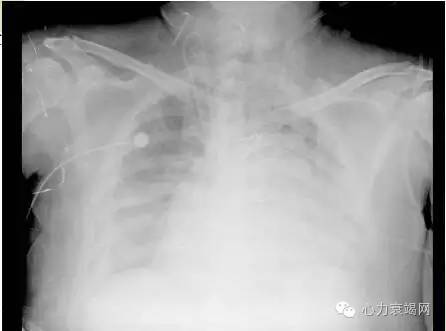

◆胸片:

两肺淤血,双侧少量胸腔积液,

右侧为著,心影增大